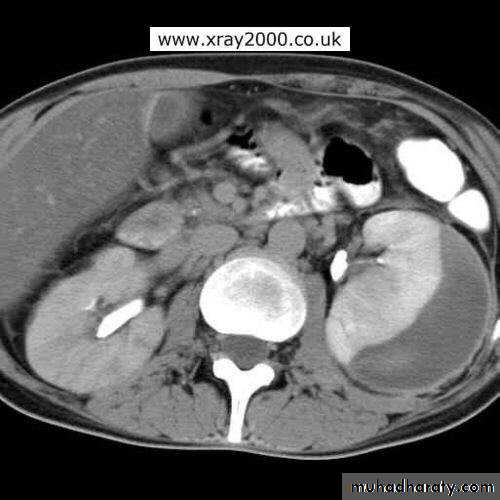

Left renal abscessCT scan: right renal abscess

CT scan: Left renal abscess

CT scan & MRI: diagnostic.